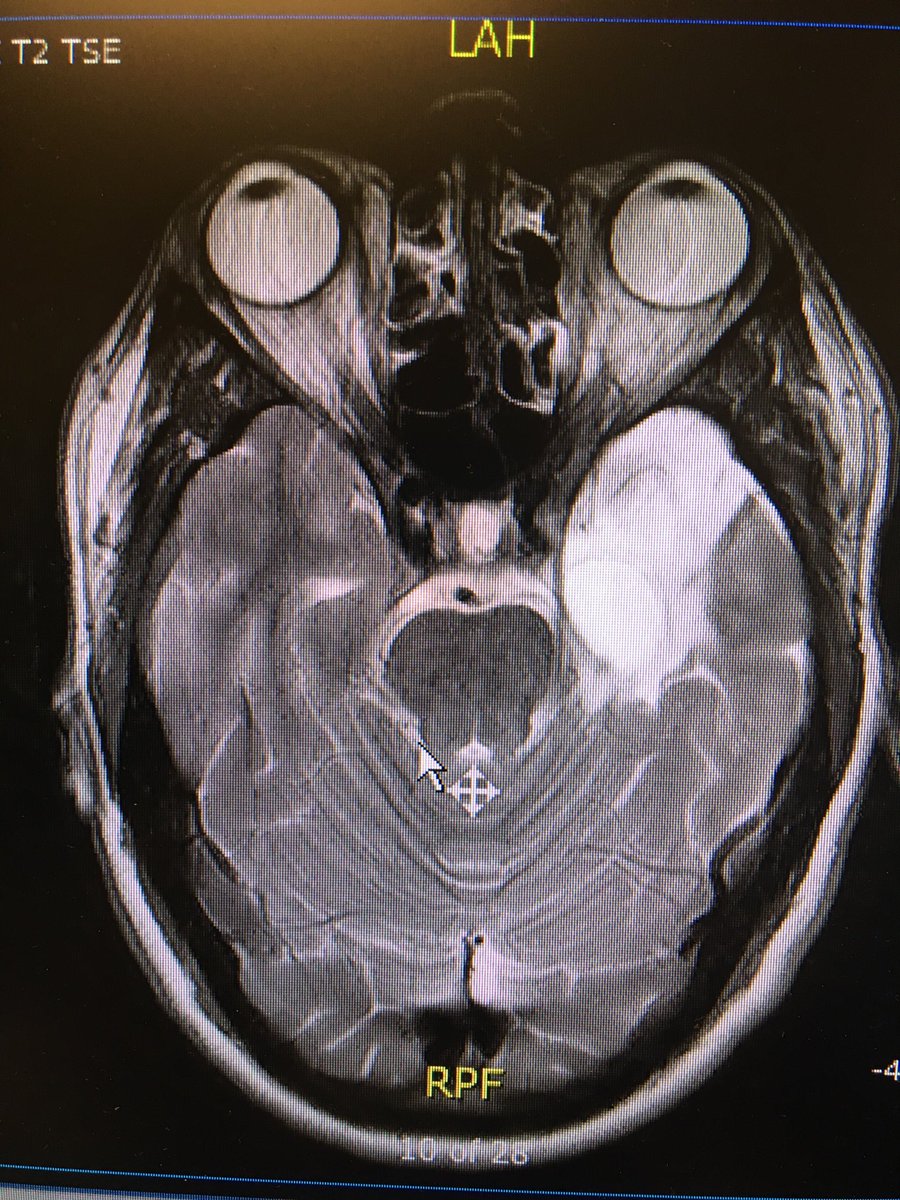

UofTMed Alum: We Were Treating Victims of Abuse, and Had No Idea medicine.utoronto.ca/news/uoftmed-a…. As a part-time medical radiation technologist, if I am suspect I mention confidentiality and encourage they speak w a social worker/MD while I am the imaging the patient...